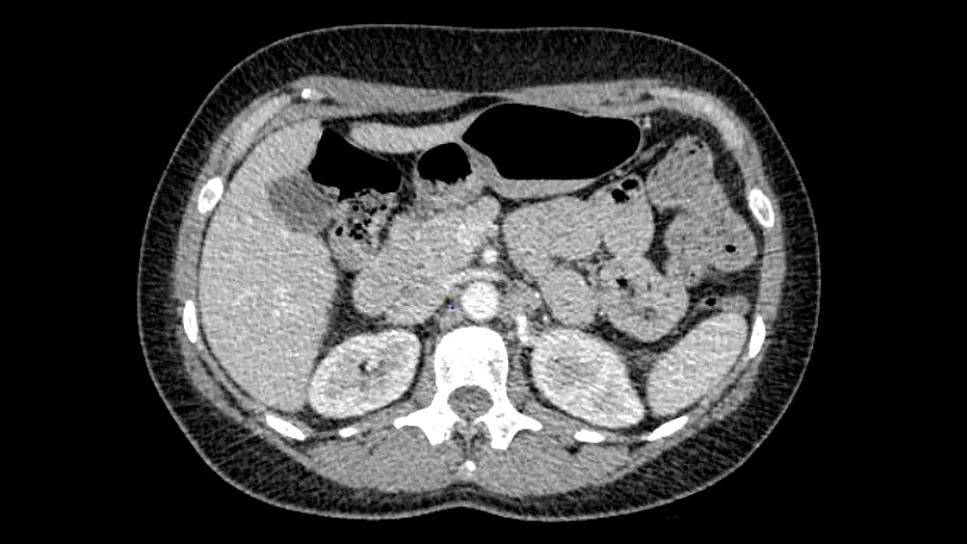

Since that time, two sets of scans showed the tumors are shrinking.

PET scans before & after therapy

Left to right: Pre-TIL, six weeks post TIL, 12 weeks post TIL